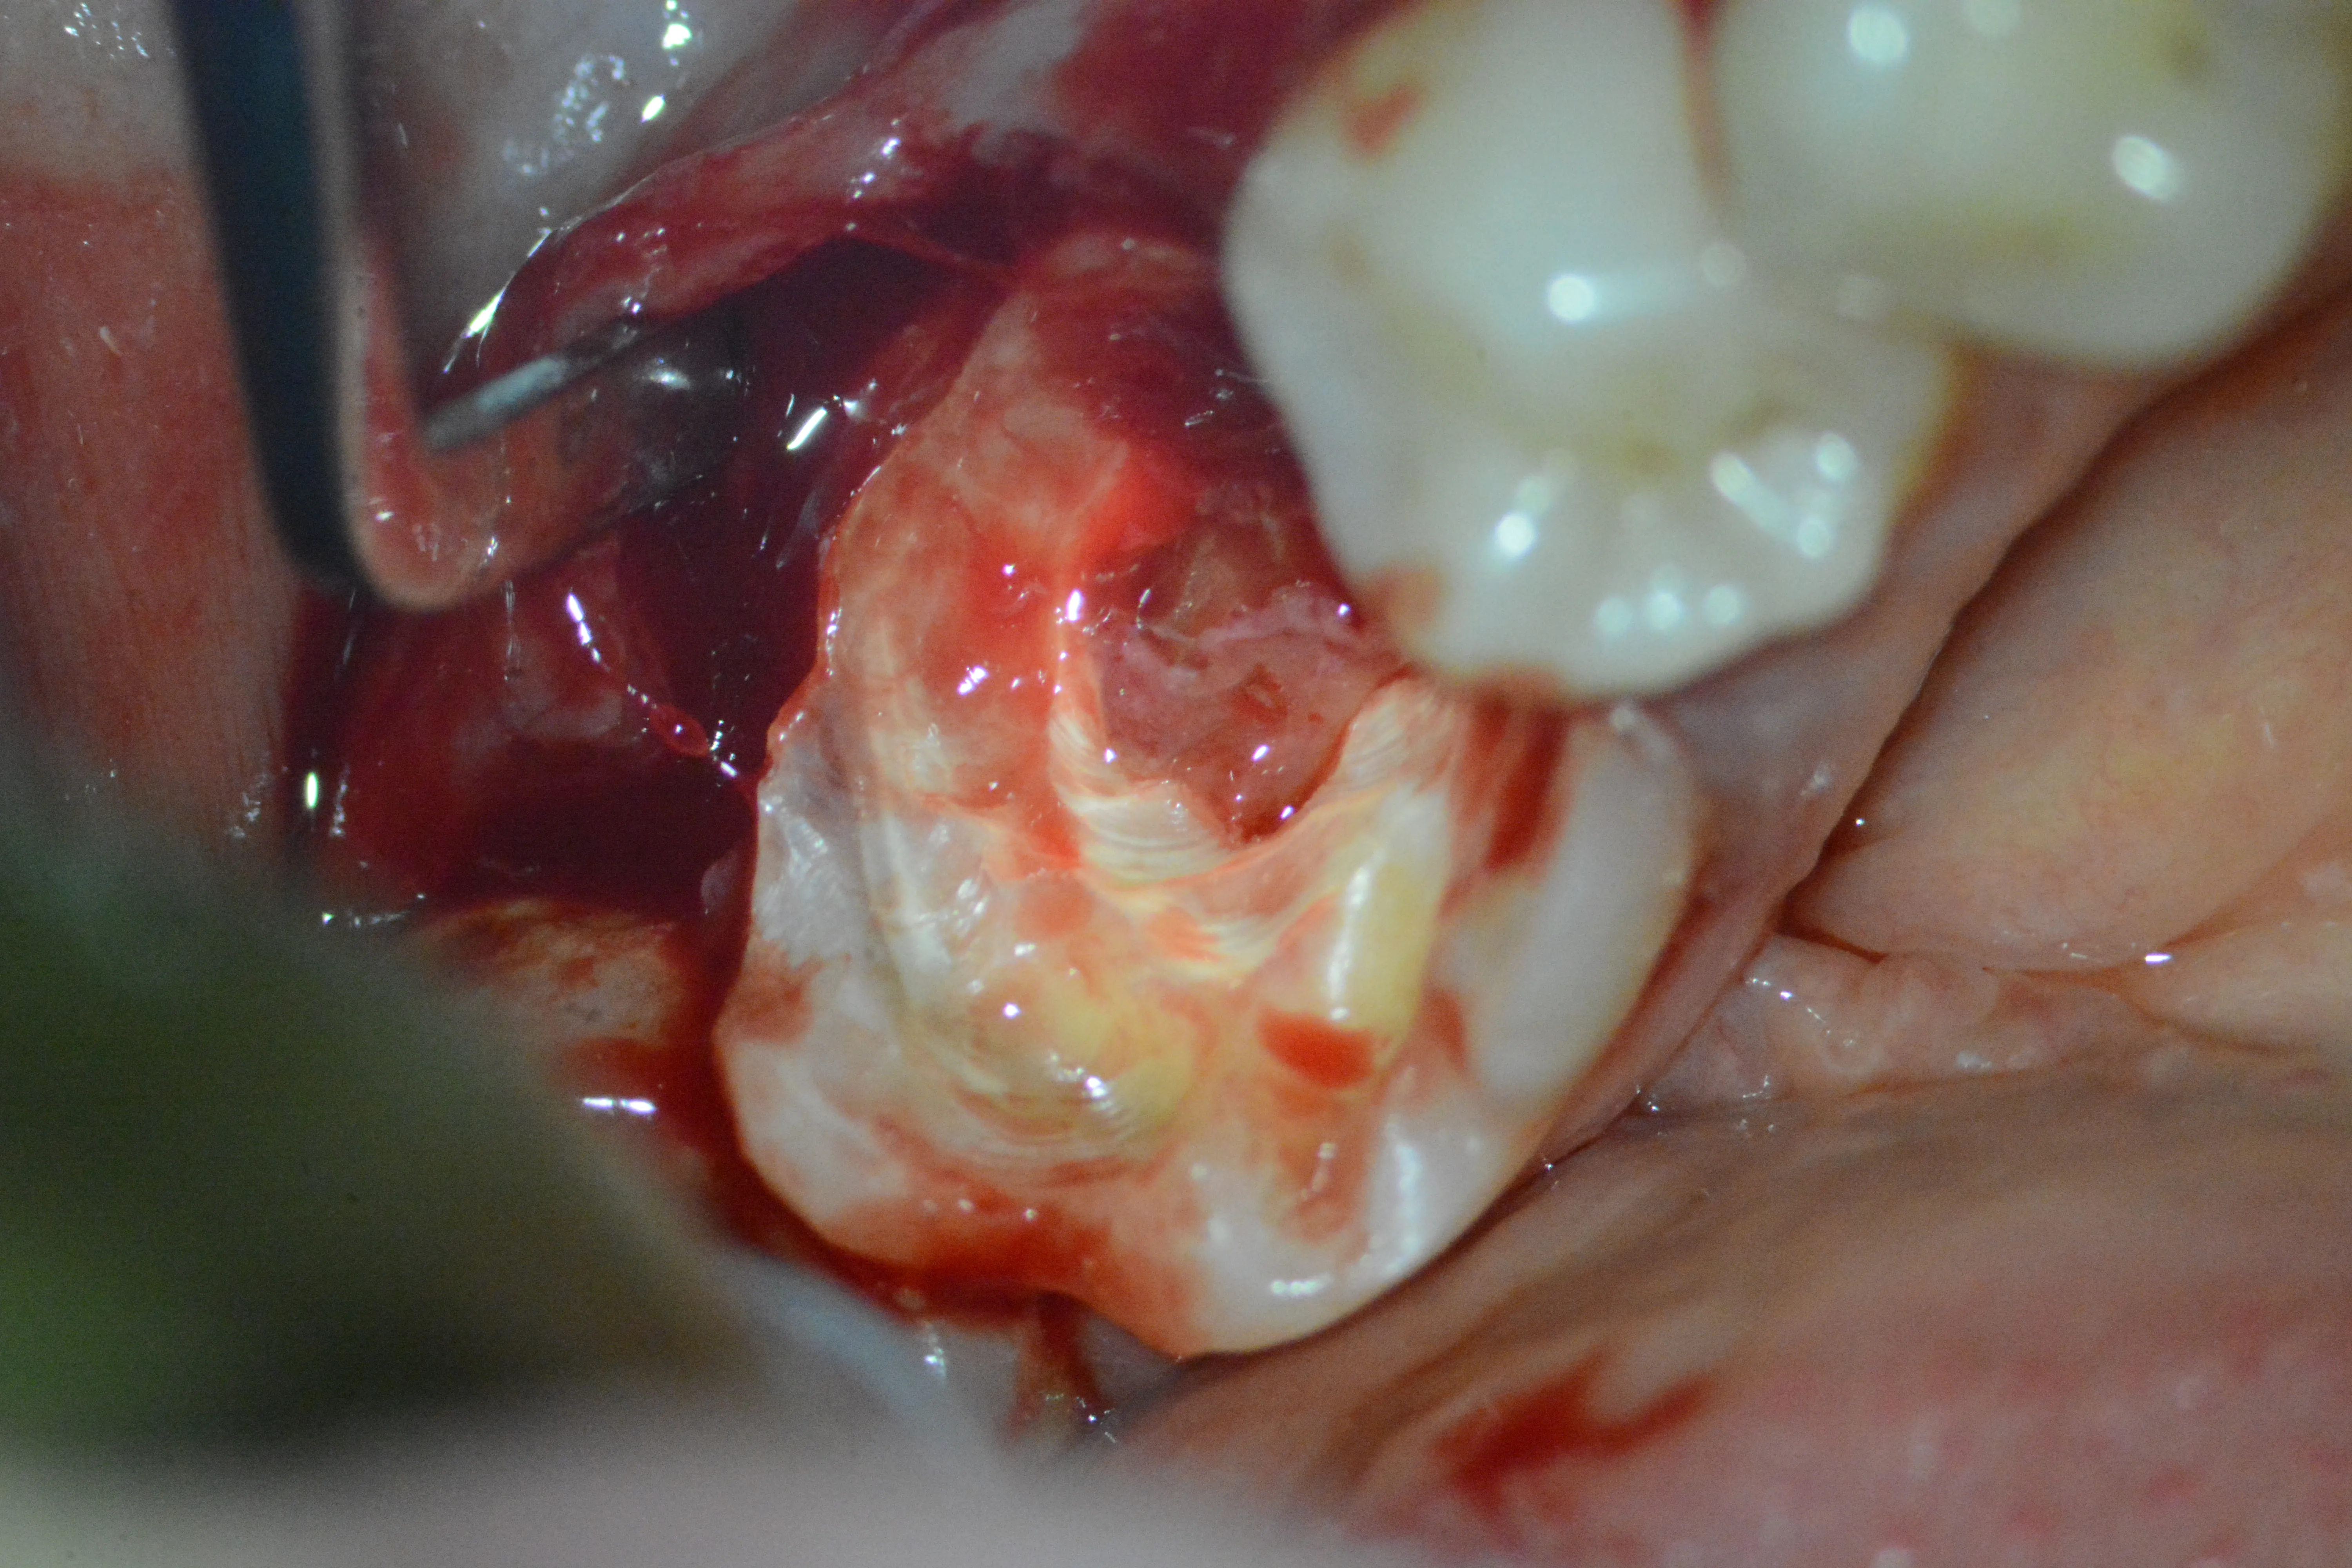

5 – Elongare coronară